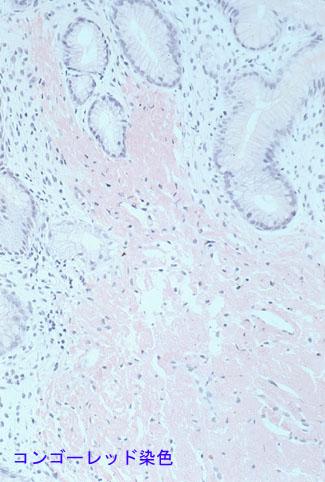

A case of gastric amyloidosis resembling IIc type early gastric cancer.

Inflammatory or ulcerative disease / lesions/Amyloidosis

Stomach/Antrum

Histology